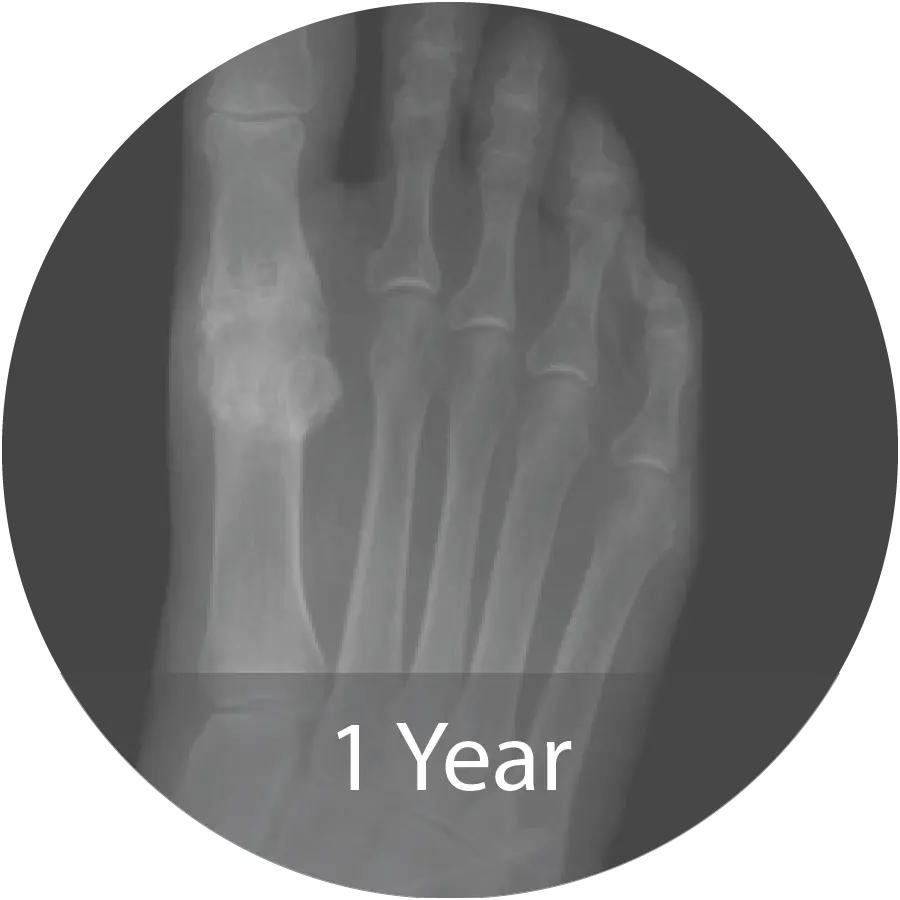

Case of 74-year-old female with hallux rigidus and multiple metallic allergies treated with 1st MTPJ arthrodesis using biointegrative hardware and InduceXT® hydrated with normal saline. Reported complete osseous consolidation at 12 months and pain-free outcome.